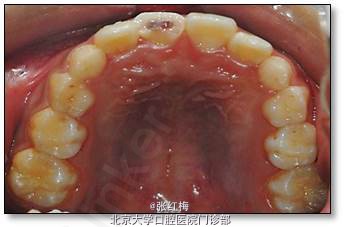

处理:11去旧充填体,11及断片牙体预备(颊侧备斜面,髓腔备固位形,舌侧备排溢道),one-coat bond+纳米树脂粘接断冠,调牙合,抛光。

随着复合树脂材料的改进和粘接材料技术的发展,使断冠粘接技术成功成为可能。其操作方法为:检测牙髓活力和松动情况,除外根折和移位,将断冠复位检查是否密合,估计缺损的大小,确定能否将断冠粘接复位。如确定可将断冠粘接复位,向患儿家长说明后,将断冠保存在生理盐水中,每3天更换1次生理盐水。

先处理牙齿松动,并进行间接盖髓,如需牙髓治疗,应先进性牙髓治疗。待以上处理结束,急性症状缓解后,进行断冠粘接。

先去掉暂时性材料,制备釉质斜面和固位抗力形态,酸蚀,涂粘接剂,用流动树脂粘接两侧断面,釉质斜面和缺损部分用复合树脂修复,去除多余的材料,调牙合,抛光。这只是一种暂时的修复方法,嘱患者不可用前牙咬硬物。

有实验证明:制备唇侧斜面可大大增加断冠粘接处的强度。